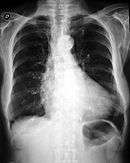

_CRUK_287.svg.png)